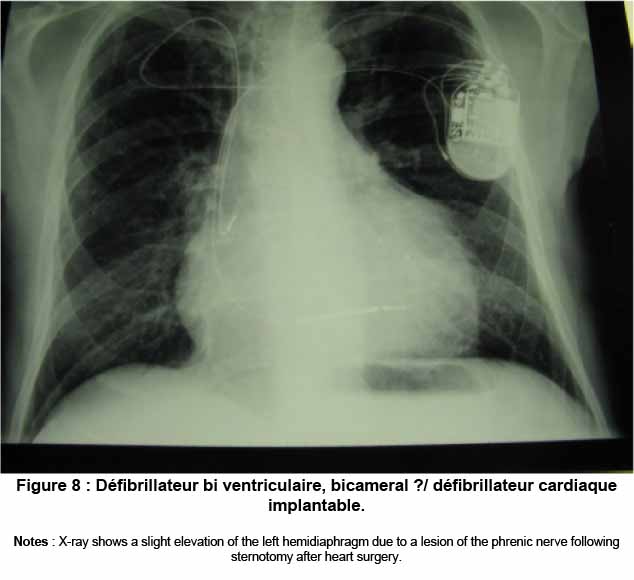

Une lésion du nerf phrénique ou du nerf vague (X° nerf crânien ou pneumogastrique, NdT) entraine un dysfonctionnement dans l’activité contractile du muscle diaphragme.[65] Le diaphragme respiratoire et les nerfs qui l’activent électriquement appartiennent au continuum fascial, qui émerge, avec le tissu méningé intracrânien, passe à travers les fascia cervicaux, endothoracique et thoraco-lombaire, impliquant également les viscères de la cage thoracique. [65,111,112] Il a été prouvé que la respiration, particulièrement la respiration forcée, affecte la motilité cérébro-spinale et la synthèse de liquide céphalo-rachidien. [100] La respiration forcée provoque un mouvement caudal du cerveau, alors que l’inspiration forcée provoque le drainage de la tête.[100] Nous pouvons avancer la théorie que si le muscle diaphragmatique ne présente pas de contractions régulières, cela affecte négativement la production de LCR, mettant en danger la santé du patient. (Figure 8)